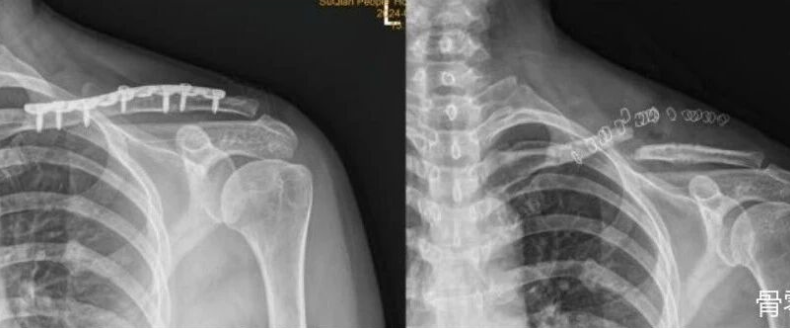

肩关节镜技术

肩关节镜手术演示